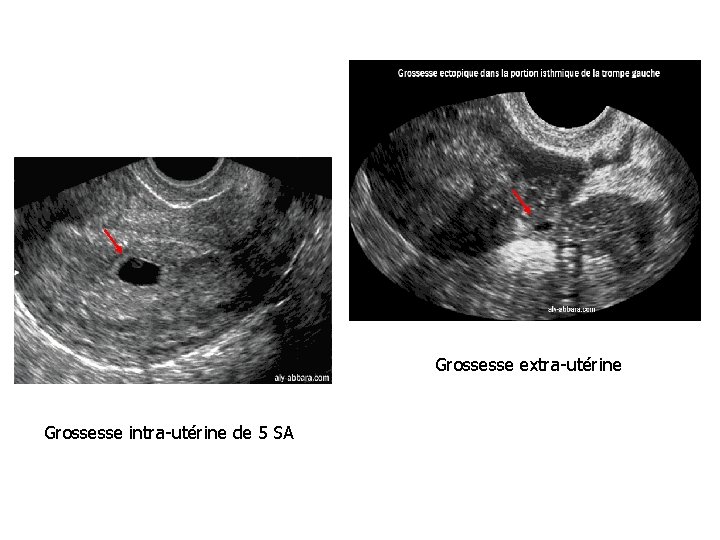

Intérêts • Localiser la grossesse (intra-utérine ou extra-utérine) En combinant l'échographie aux dosages de h. CG plasmatique, il est admis qu'une grossesse évolutive intra-utérine est visible : - par l'échographie par voie abdominale à partir d'un taux plasmatique de βh. CG égale ou supérieur à 2000 m. UI/ml ; - par l'échographie par voie endovaginale à partir d'un taux plasmatique de βh. CG égale ou supérieur à 1500 m. UI/ml. • Dater le début de la grossesse Plusieurs mesures en fonction de l'âge de la grossesse : - entre 4, 5 et 7 SA : mesure de la longueur maximale du sac gestationnel - entre 7 et 12 SA : mesure de la longueur cranio-caudale (LCC) (degré de précision de cette mesure est de l'ordre de ± 3 jours)

Grossesse extra-utérine Grossesse intra-utérine de 5 SA